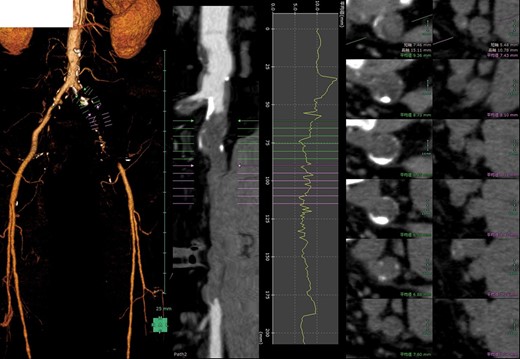

He underwent an elective laparoscopic abdominoperineal resection with a lithotomy position. There was no vascular injury or compression with laparoscopic forceps as far as we were able to recognize retrospectively based on the laparoscopic video and the memory. The duration of surgery was 4 hours and 48 minutes. Blood loss was estimated 100 ml, the urine volume was only 50 ml during the operation. In-out balance during operation divided body weight and time of operation was 6.38 ml/kg/h. The patient reported a severe pain in the left leg, when he woke up post-operatively. The left leg was pale and cold, associating sensory abnormality and motor dysfunction; left pedal and popliteal pulses were absent. A CT scan revealed the contrast interruption of left common iliac artery (CIA) over 11.5 cm and suspected to be due to an arterial thrombosis (Fig. 2). Under the local anesthetic technique, the left femoral artery was exposed and performed thrombectomy with a 5Fr Fogarty catheter. After a new clot was removed, aortography revealed persistent stenosis in left iliac artery. Consequently, a Percutaneous transluminal angioplasty (PTA) with stent (Express LD 8 × 37 mm) was added (Fig. 3) via left femoral artery. Blood perfusion in his left leg improved markedly immediately post PTA. The patient was transferred to the intensive care unit for two days due to the complications with a rhabdomyolysis (creatinine phosphokinase up to 23 598 IU/l). The patient started walking 5 days post-surgery, however, the patient was left with the numbness in his left lower leg. A heparinization had been commenced on the postoperative day 1, then this was switched to the cilostazol prior to the discharge for home. We note that the patient continued reporting the left lower leg numbness even one year past the surgery.

Postoperative 3D-contrast enhanced CT revealed the complete obstruction of left common iliac artery (CIA). The sagittal section through the left iliac artery and the graph of left CIA’s internal diameter showed significant stenosis.